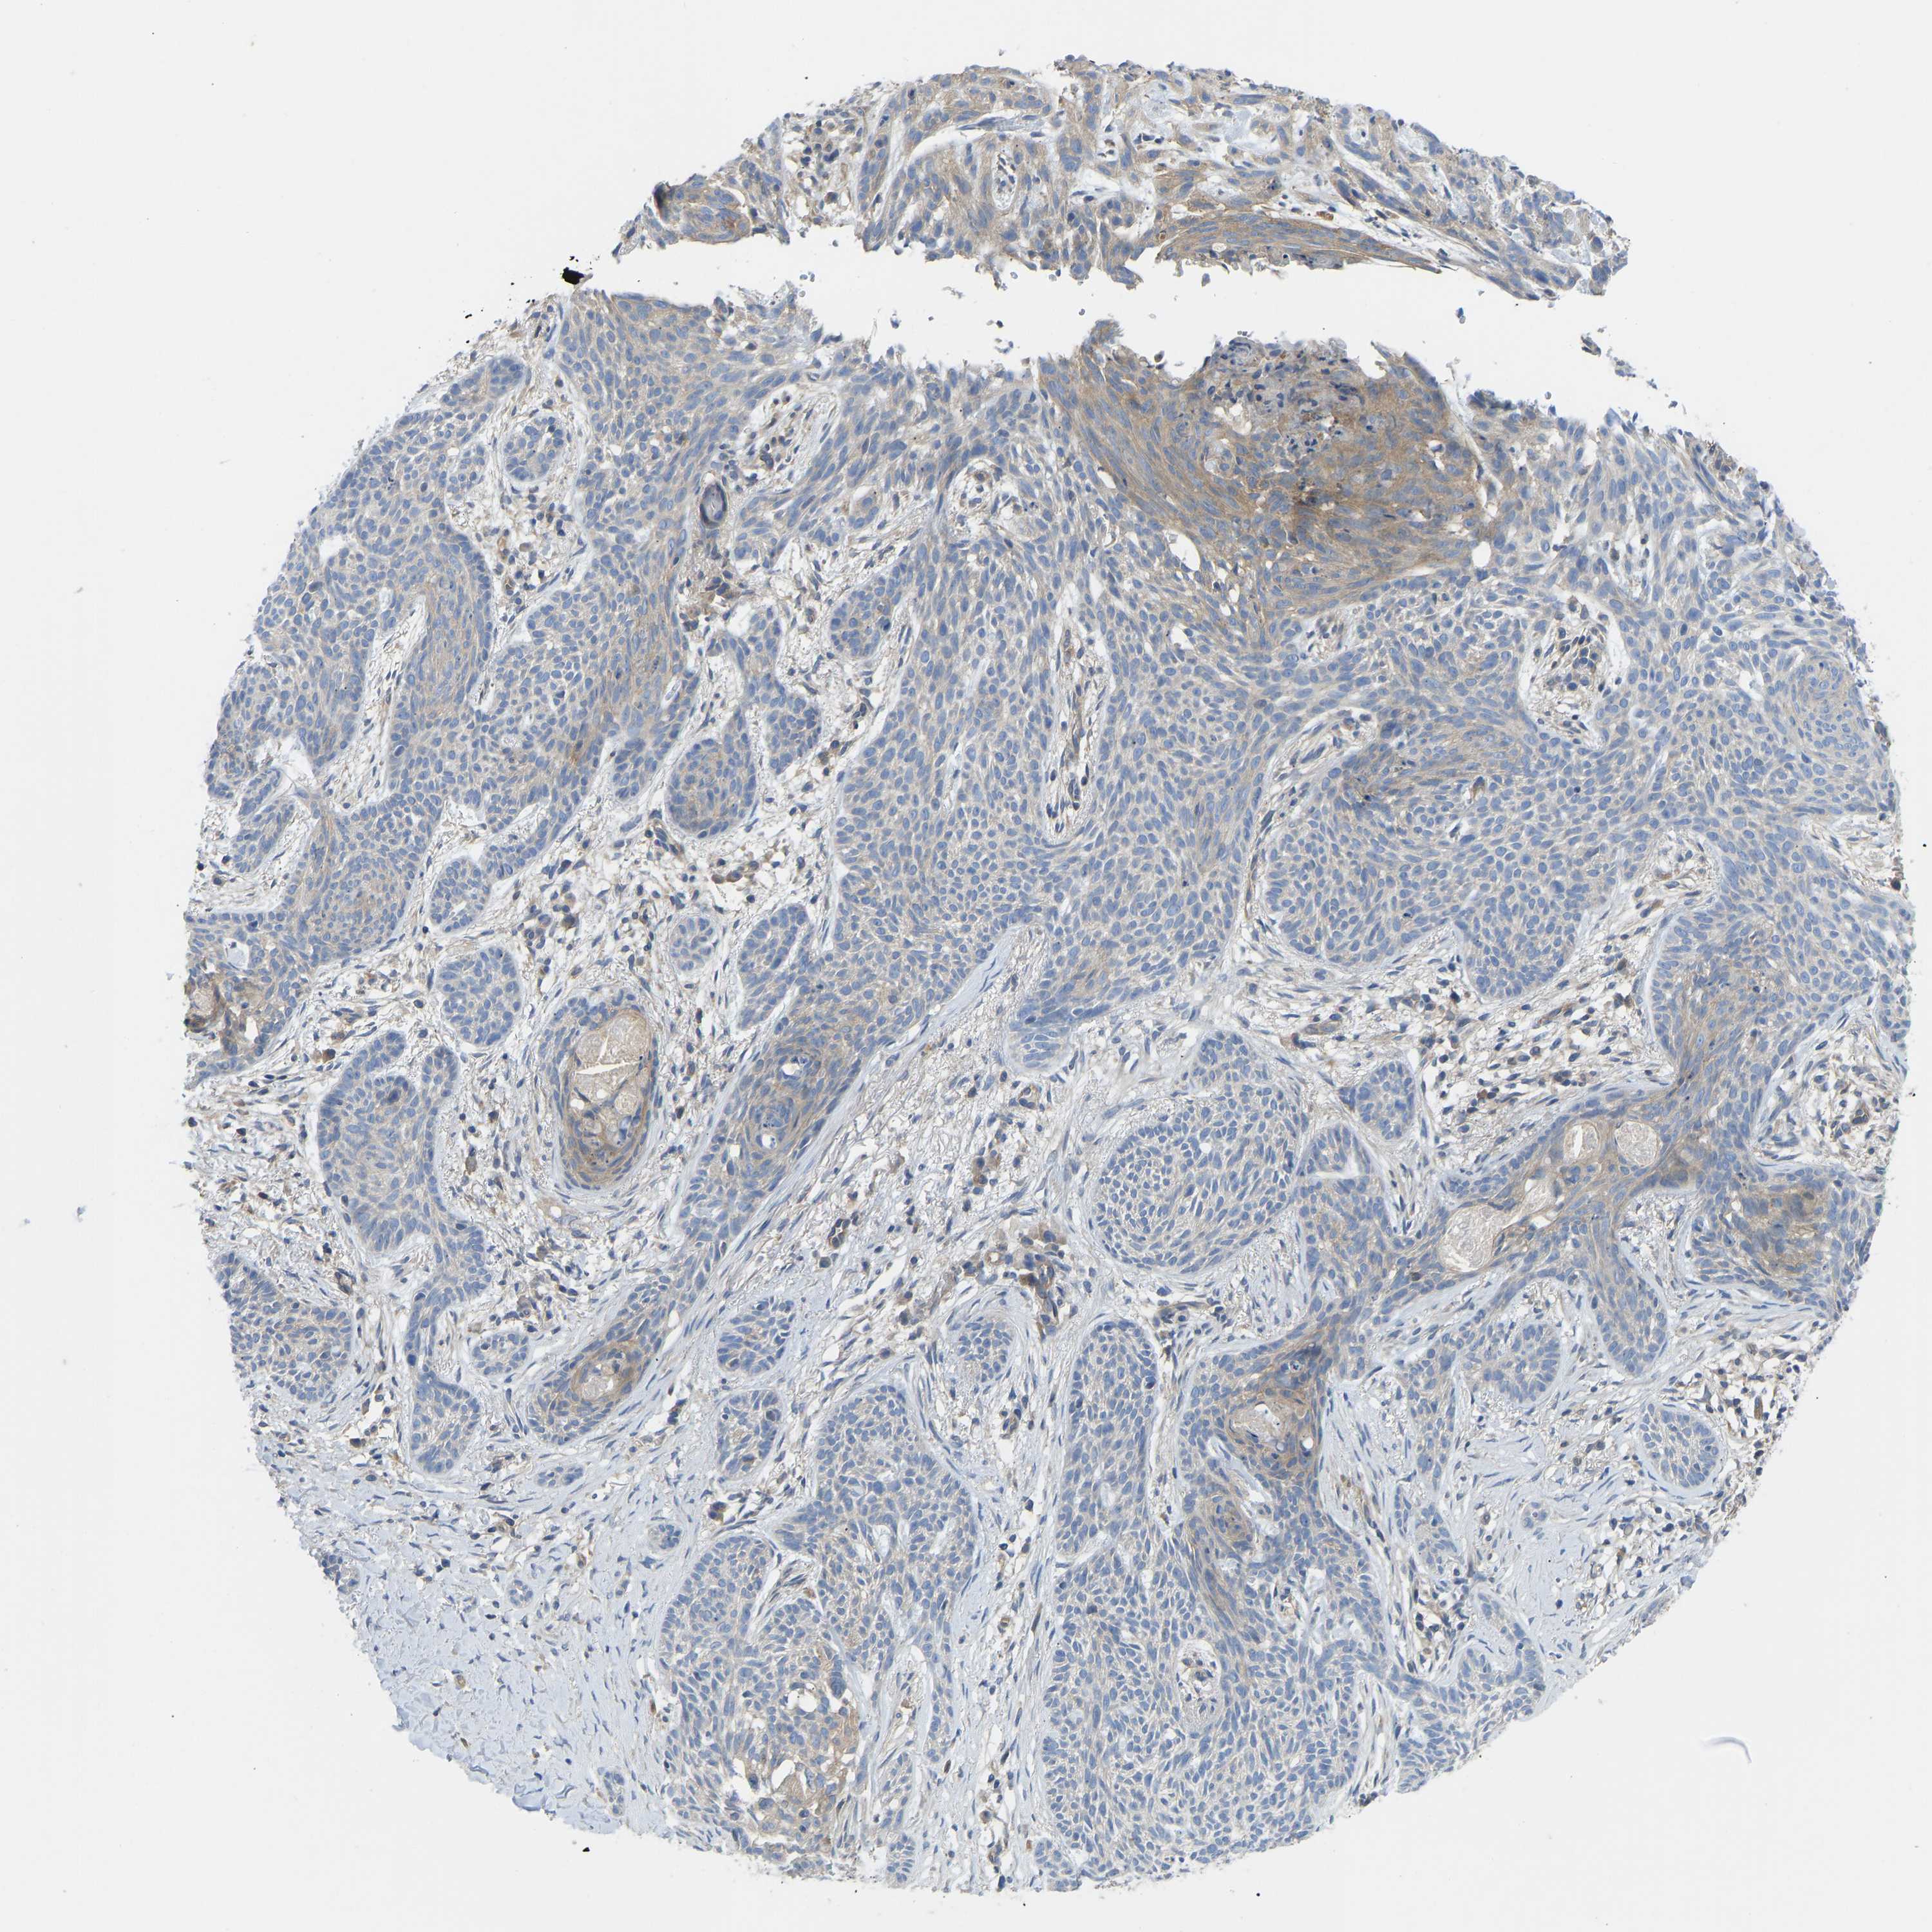

SKIN CANCER - Protein expressioni

A mouse-over function shows sample information and annotation data. Click on an image to view it in a full screen mode. Samples can be filtered based on level of antibody staining by selecting one or several of the following categories: high, medium, low and not detected. The assay and annotation is described here.

Each image is clickable and will lead to virtual microscopy that enables deeper exploration of all samples and also displays staining intensity scores, fraction scores and subcellular localization as well as patient and tissue information for each sample.

Antibody CAB018581

Squamous cell carcinoma, NOS